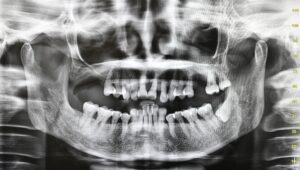

盧:戴口罩不會加快牙菌膜繁殖生長,亦不會導致蛀牙。牙菌膜是細菌及細菌新陳代謝的產物,若不斷為細菌提供養分,如糖分,就會加快牙菌膜滋生。應留意,口腔健康情况與日常口腔衛生息息相關,如不想有蛀牙,應加強管理口腔衛生;亦應定期到牙醫診所檢查牙齒。

口腔衛生變差 牙石增多牙肉發炎

他續稱,受疫情影響,不少客人推遲牙科檢查,較常出現口腔衛生變差、牙石增多及牙肉發炎的問題;部分人如未有按時定期做牙科檢查,更可能有蛀牙、牙痛等問題。惟就他觀察,未有發現因延期檢查而有特別大的口腔問題,形容「口腔情况仍在牙醫處理範圍以內」。及至今年初,牙科服務已有八至九成回復正常。他建議,如牙科檢查曾因疫情改期,可趁現時疫情放緩,重新預約服務。